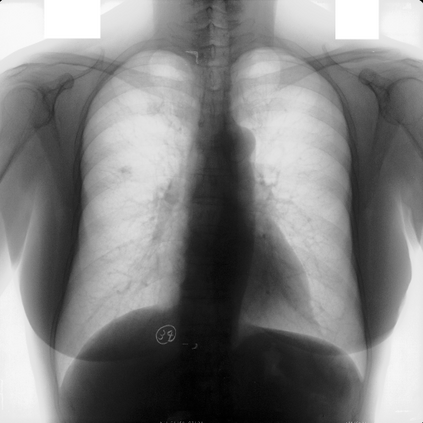

Multi-organ segmentation of X-ray images is of fundamental importance for computer aided diagnosis systems. However, the most advanced semantic segmentation methods rely on deep learning and require a huge amount of labeled images, which are rarely available due to both the high cost of human resources and the time required for labeling. In this paper, we present a novel multi-stage generation algorithm based on Generative Adversarial Networks (GANs) that can produce synthetic images along with their semantic labels and can be used for data augmentation. The main feature of the method is that, unlike other approaches, generation occurs in several stages, which simplifies the procedure and allows it to be used on very small datasets. The method has been evaluated on the segmentation of chest radiographic images, showing promising results. The multistage approach achieves state-of-the-art and, when very few images are used to train the GANs, outperforms the corresponding single-stage approach.